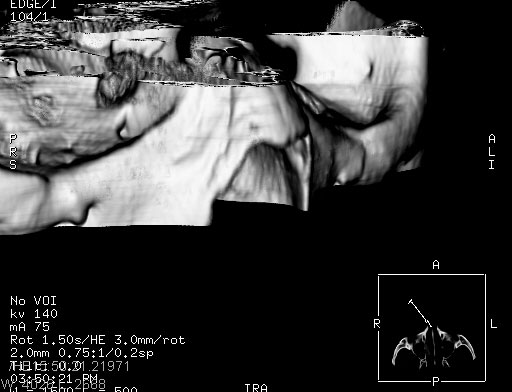

患者,男,以头面部外伤后头疼1小时为主诉入院,患者1小时前被他人打伤头部及左侧面部,眼睑无水肿,左侧面部肿胀压疼,未触及骨擦音。专科检查:耳鼻喉未见异常。

ct:平扫+冠扫:双侧鼻骨对比,冠扫s6#示右侧鼻骨尖部可见线状低密度影,边缘光滑,并见硬化.软组织未见肿胀.

诊断意见:鼻额缝(鼻骨与上颌骨额突缝),但个别同志认为是骨折.因此请同行们会诊.多谢了!

正常鼻颌缝。软组织无肿胀。鼻腔无积液积血。鼻骨光滑规整无中断。均不支持骨折。

正常的,双侧对称.边缘光整,且逢等宽.

正常鼻颌缝。软组织无肿胀。鼻腔无积液积血。鼻骨光滑规整双侧对称。均不支持骨折。